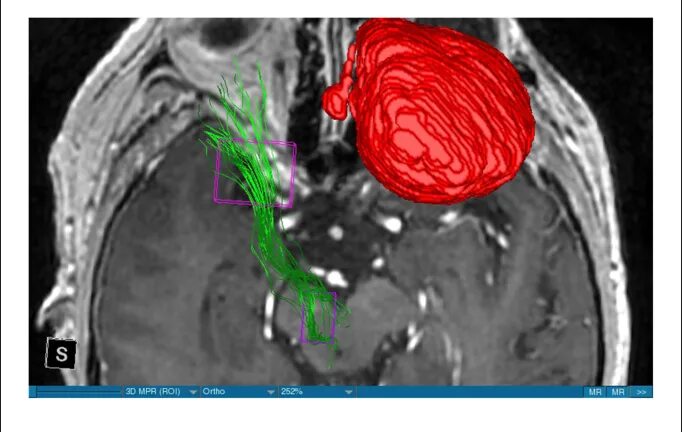

Diffusion tensor